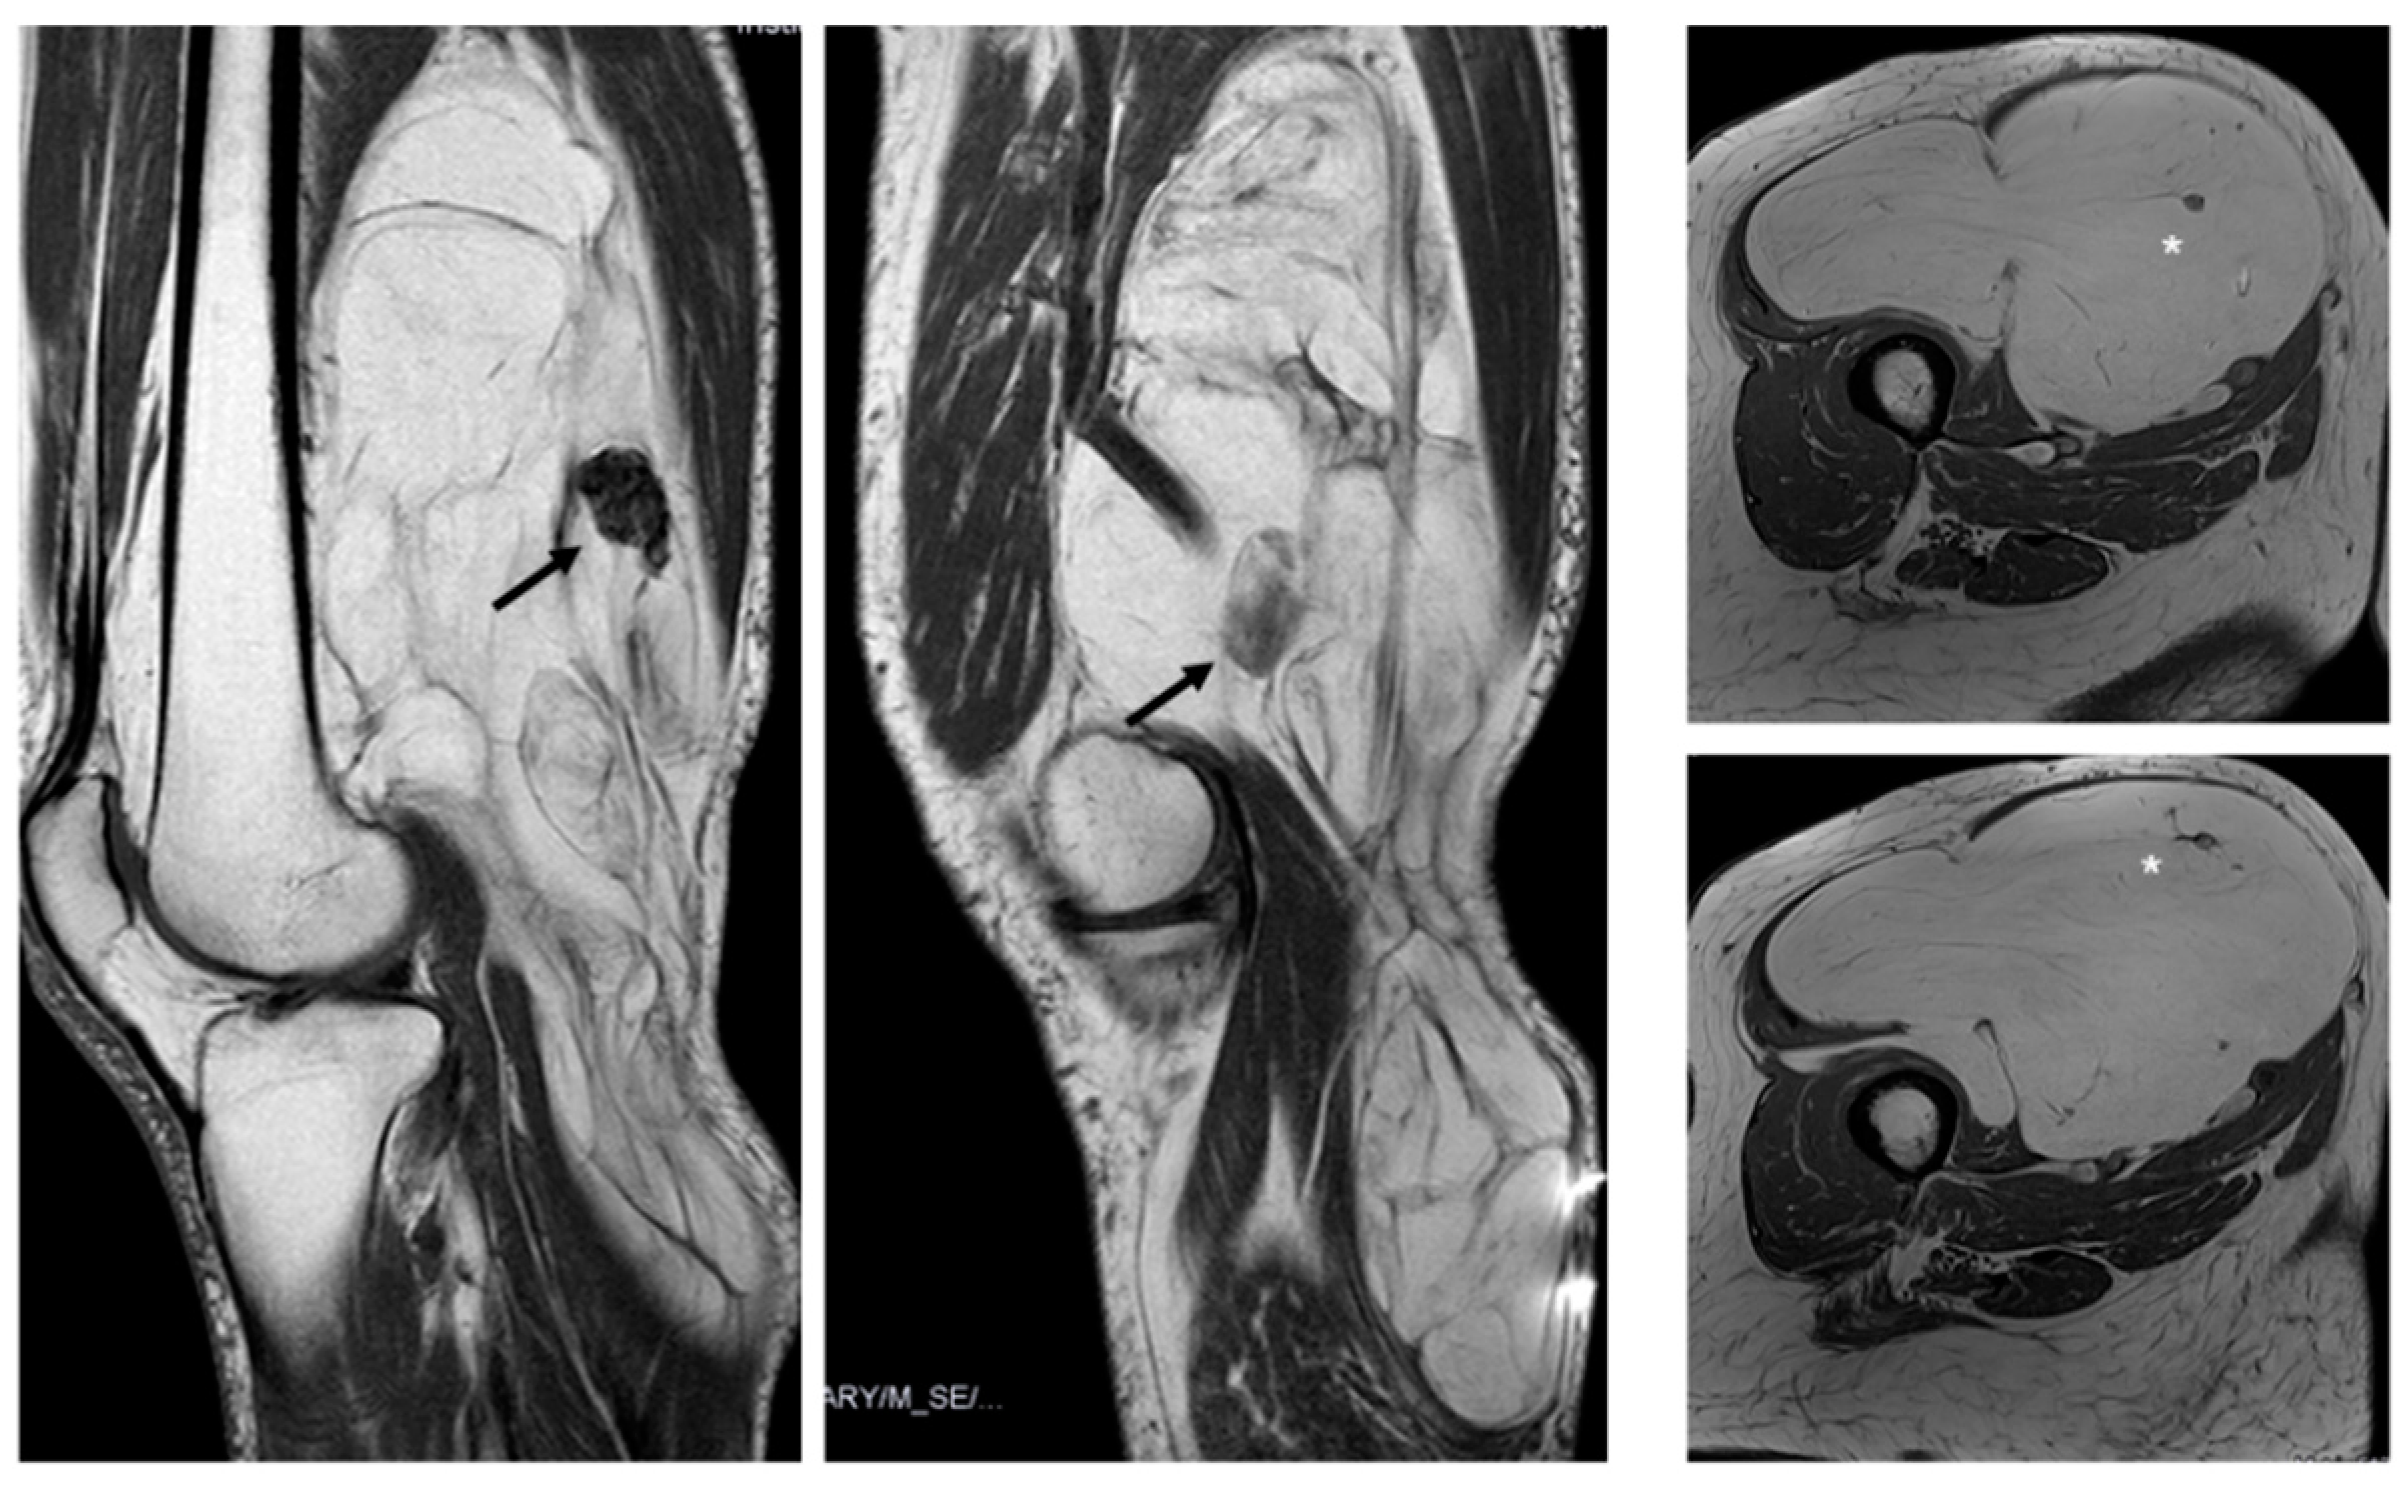

Figure 6. Nodules. Sagittal T1W images show a deep lipomatous mass in the popliteal fossa, measuring 27 cm along its long axis and with two non-fat nodules (arrows) Diagnosis: ALT (MDM2 positive). Axial T2W images present a lipomatous tumor in quadriceps, with two non-fat nodules (asterisks) Diagnosis: ALT (MDM2 positive).

There was typically more than one non-fat nodule in ALT, while lipomas usually had only one (Figure 6). Unlike other studies, which suggested that non-fat nodules larger than 1 cm in diameter are an important discriminator favoring ALT over lipoma [17], our findings did not support this distinction.